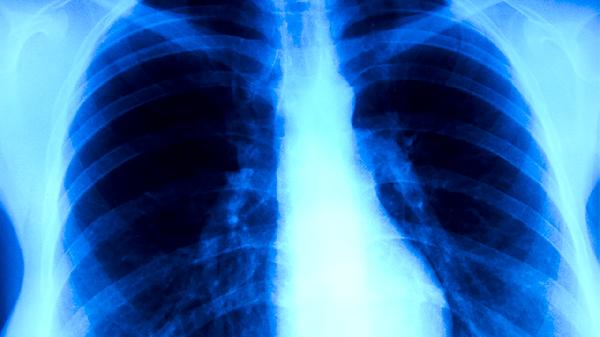

得了肺结核有哪些症状 浅析肺结核的四个主要症状

肺结核的主要症状有咳嗽、咳痰、发热、盗汗等。肺结核是由结核分枝杆菌感染引起的慢性传染病,主要通过呼吸道传播,患者需及时就医并接受规范治疗。